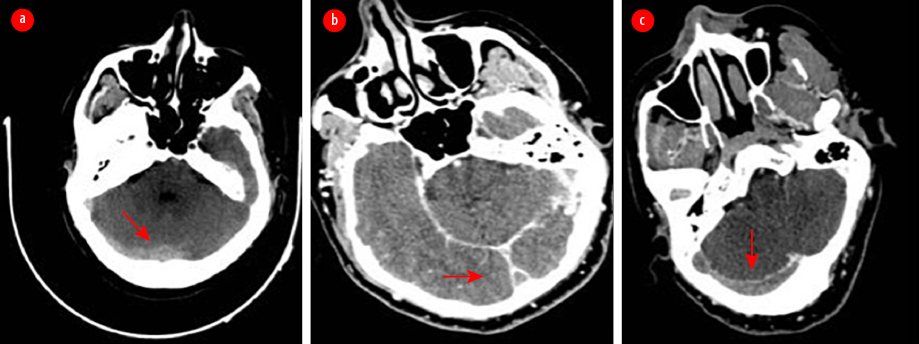

Magnetic resonance imaging of the brain demonstrated increased signal intensity in the right sigmoid sinus and right transverse sinus [Figure 3]. The echocardiogram was normal. Holter monitoring demonstrated sinus bradycardia. Therapeutic anticoagulation was initiated, and the patient recovered clinically despite continuing to experience mild headaches and dizziness. Cardiology evaluation revealed persistent symptomatic bradycardia with sinus bradycardia ranging from 30 to 45 beats/min with pauses lasting 4–5 seconds. After diagnosis of SSS, the patient was transferred to the cardiac care unit for pacemaker implantation. After 24 hours of observation, the post-procedure period was uneventful, and telemetry revealed sinus rhythm without a pacing beat. The recorded heart rate was within the normal range.

Figure 3: (a) An axial T2-weighted MRI demonstrates an area of abnormality with increased signal intensity in the right sigmoid sinus consistent with cerebral venous thrombosis (CVT). (b) Fluid-attenuated inversion recovery weighted MRI demonstrates a hyperintense signal in the right transverse sinus. (c) A coronal T2-weighted MRI shows hypersignal intensity in the superior sagittal sinus. (d) A sagittal contrast-enhanced T1-weighted image shows filling defects along the superior sagittal sinus and involving the other cerebral sinuses, indicating extensive CVT.